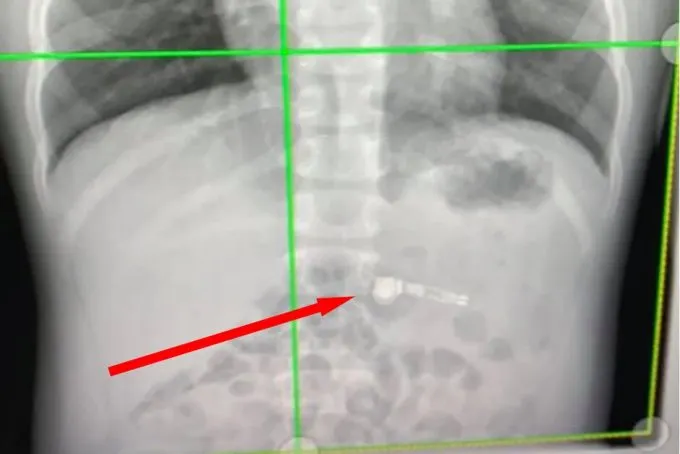

Ребёнок сам пожалел, что небезопасно играл с гаджетом. Он сказал матери, что сильно перепугается, если AirPods вдруг начнут играть внутри него. Медики сделали рентген, подтвердили нахождение инородного тела и заключили, что наушник должен выйти естественным образом. Так и случилось.